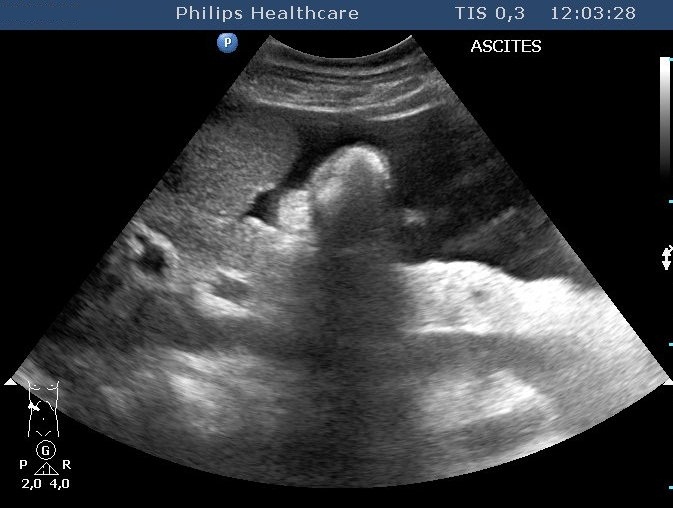

No direct association among the extent of fibrosis, the degree of the dysfunction and the ultrasound morphology was detected, normal liver structure can be observed in case of an extended encephalopathy as well. The right lobe size can decrease, left lobe and caudate lobe hypertrophy develops. Lateral segment of the left lobe can increase besides the decrease of the medial segment's size. The fibrosis itself does not change the parenchyma reflectivity. Increased reflection can be observed if it accompanies with fat deposition as well. On the other hand, rough echostructure, inhomogenecity can be observed in the parenchyma due to the miliary (4-5 mm or smaller) regenerative nodules. Bigger nodules result extensive surface incongruences (Figure 14).

Figure 14: Liver chirrosis, nodular surface, ascites

The regenerative nodules can appear as moderately hypoechoic lesions, mimicing hepatocellular carcinoma which develops more frequently based on cirrhosis related to B and C viral hepatitis. The nature of the developing nodule can only be clarified by biopsy in some cases. Small amount of free abdominal fluid (ascites) can be imaged well by US. Signs of portal hypertension can be also recognised very well, however, the exact determination of the circulation statuses goes over the possibilities of the rutine US examination obviously. In this case, an accessory color duplex US examination using an appropriate top category device is necessary.

More importantly we can rely on the evaluation of the morphological lesions such as the nodular appearence of the liver parenchyma with the distorted vessels, enlarged caudate lobe and the secondary signs such as: dilatated collateral vessels (which can be imaged exquisitely by MR with signal void), splenomegaly and ascites.

MR angiography images the collateral and portal vessels replacing the invasive DSA. MRI is also suitable for the control of the surgically prepared portocaval shunts. Extension and degree of the ascites can be clearly imaged by MRI (T2-weighted images).